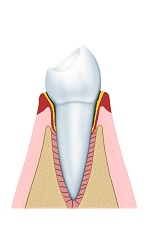

Stadium 2: Parodontitis

Bij parodontitis breidt de tandvleesontsteking zich uit naar de rand van het tandvlees en/of het kaakbot. Het kaakbot kan worden aangetast waardoor tanden en kiezen los gaan zitten of zelfs uitvallen.

Parodontitis gaat niet vanzelf over. Om dit te genezen zal er een paro-protocol moeten worden opgestart. Onze tandarts of mondhygiënist geeft u graag gedetailleerder advies.

Geringe parodontitis

Geringe parodontitis

Vergevorderde paradontitis

Vergevorderde paradontitis